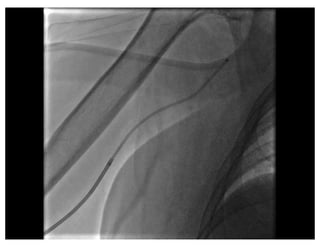

Traversing a radial loop

Patel’s  Atlas  of Transradial  intervention  – The Basics. 2007 Traversing a radial loop